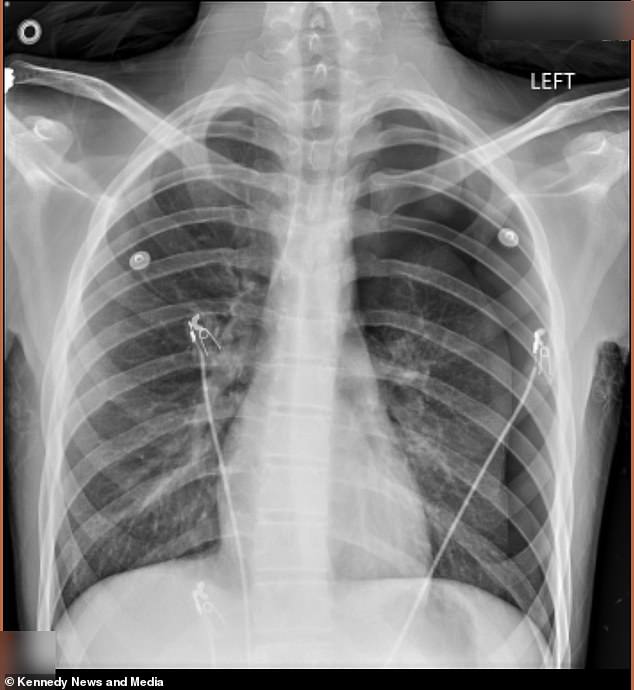

It started as a way to fit in. Cameron Vann, known as Dodge, was 15 when he picked up vaping at school. His mother, Crystal Vann, never saw the device in his hands. He hid it, kept it secret, and told himself it was just a phase. But two years later, the consequences of that decision were life-changing. In September 2025, Dodge emerged from the school bus pale, trembling, and clutching his back. His mother didn't hesitate. She rushed him to the emergency room, where a chest x-ray revealed a 50 percent collapse of his left lung. The diagnosis—pneumothorax—was a medical term for a condition that felt anything but academic to Crystal. It was a gut punch. The doctors had to insert an 18-inch tube into his chest to remove the trapped air and give his lung a chance to expand again. But the damage was already done. Dodge, who had kept vaping, didn't stop. He didn't tell his mother. He didn't think it could hurt that badly.

The second collapse came in January 2026. This time, the pain was worse. Dodge called his mother from school, gasping for breath, unsure if the agony in his chest was from the vaping or something else. Crystal arrived at the hospital, heart pounding, and watched as doctors scrambled. They told her the same thing: he could have died in the lobby. The second surgery was more severe. A pleurodesis, a procedure where the lining of the lung is scraped and blebs—air-filled blisters—are stapled to the top of the lung. The goal was to reattach the lung to the chest wall and prevent future collapses. For Crystal, it was a nightmare. She kept asking the same question: Why him? Her son, a kind and passionate kid with a big heart, had been reduced to a patient in pain, haunted by the fear of another collapse.

Vapes work by heating a liquid that contains nicotine, flavorings, and a cocktail of toxic chemicals. When inhaled, the vapor delivers these substances deep into the lungs, including formaldehyde, acetaldehyde, and other volatile organic compounds linked to cancer. Over time, this damage can lead to DNA mutations and inflammation, increasing the risk of disease. For Dodge, the damage was visible on an x-ray. His left lung, once a vital organ, now bore the scars of his choices. His mother, Crystal, has become an advocate, calling for a nationwide ban on vapes. 'I say ban on all vapes,' she said. 'I don't want another kid going through it. Don't do it just to be cool.'